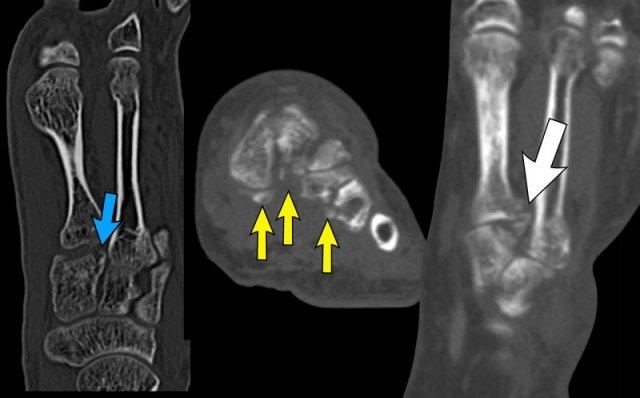

case 2 – chronic pain post ankle sprains

The findings are:

- mỏm trước xương gót kéo dài khớp với xương thuyền.

- the diagnosis is calcaneonavicular coalition.

Xương gót và xương thuyền thường không khớp với nhau.

Trong trường hợp liên kết xương, có thể thấy một cầu xương nối liền hai xương này.

Compare to the normal situation.

Với liên kết xơ hoặc sụn, các xương nằm gần nhau, cả hai đều có bề mặt không đều, và phần trước trong của xương gót bất thường bị giãn rộng hoặc phẳng dẹt.

Trên phim X-quang tư thế bên, sự kéo dài của phần lưng trước xương gót có thể mô phỏng hình ảnh mũi con thú ăn kiến.

Thiểu sản xương sên đôi khi được quan sát thấy trong liên kết gót-thuyền.

Trên CT, chúng ta thấy sự hợp nhất giữa xương gót và xương thuyền.

CT cho thấy xơ cứng xương và các nang dưới sụn như là dấu hiệu của ‘ma sát’ do khớp tân tạo.

MRI cho thấy phù tủy xương như là dấu hiệu của sự hợp nhất có triệu chứng.